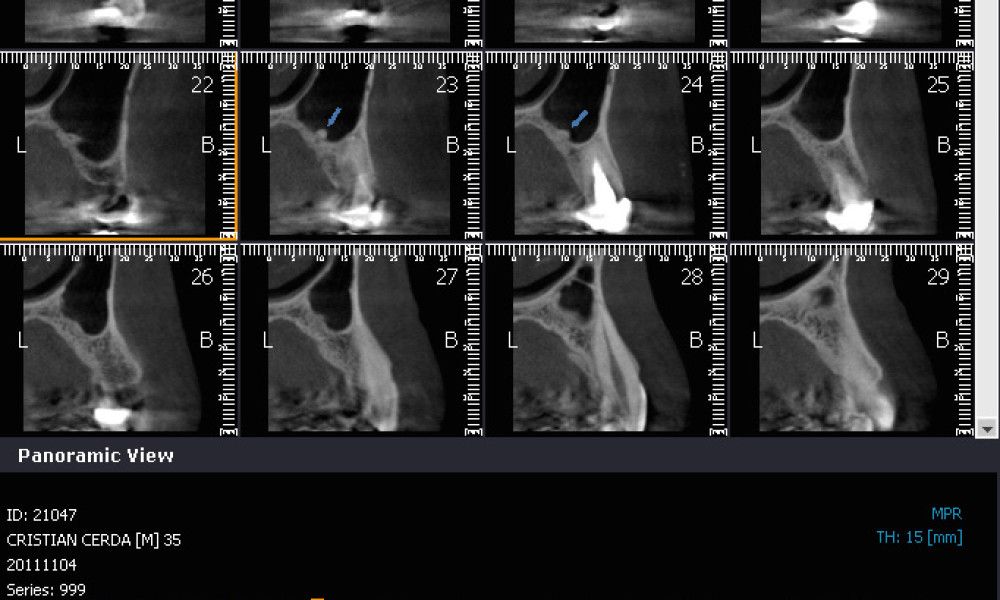

El estudio imagenológico evidencia una pérdida ósea severa en altitud y grosor, situación que complejiza la colocación de un implante. Se analizan alternativas de tratamiento y se opta por una vestibuloplastía mediante autoinjerto conectivo de mucosa palatina que se reposiciona sobre la zona del defecto óseo. Además se realiza retratamiento de ambas PFP, ahora en zirconia, por motivos estéticos y oclusales. Se realizan controles posteriores para evaluar la respuesta gingival a la vestibuloplastía.